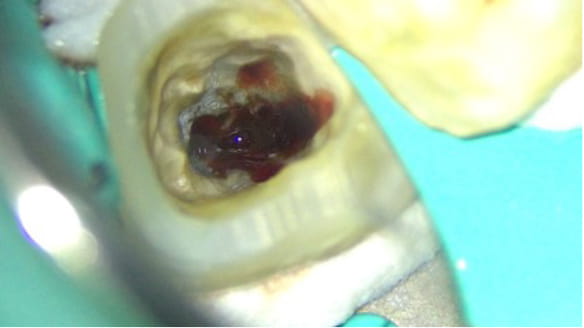

外すと中がドロドロに虫歯に感染していました。

折れて残っていた機具を除去

根管の中を洗浄し、無菌に近い空の状態にした。

歯の中を触ると膿がかなりでてきました。

根管の中が無菌に近い状態になるように洗浄を繰り返します。